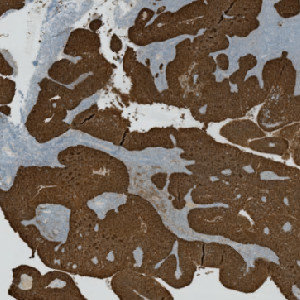

CK5 stained slide.

Two serial sections stained for Ki-67 and CK5, respectively, must be used in this APP. Tumor regions are identified automatically on the CK5 stained slides using the VirtualDoubleStaining™ technique, and the outlined tumor regions are overlaid on the Ki-67 stained slide, thus automatically identifying tumor regions.

The auxiliary APP ’01 Tumor Detection” is used for automatic tumor detection.

Tumor areas are automatically detected from the CK5 slide and outlined as regions of interest (ROIs). The ROIs are superimposed onto the aligned Ki-67 tissue slide to outline the tumor region on the Ki-67 slide. The subsequent analysis is now limited to the inside of the tumor regions only.